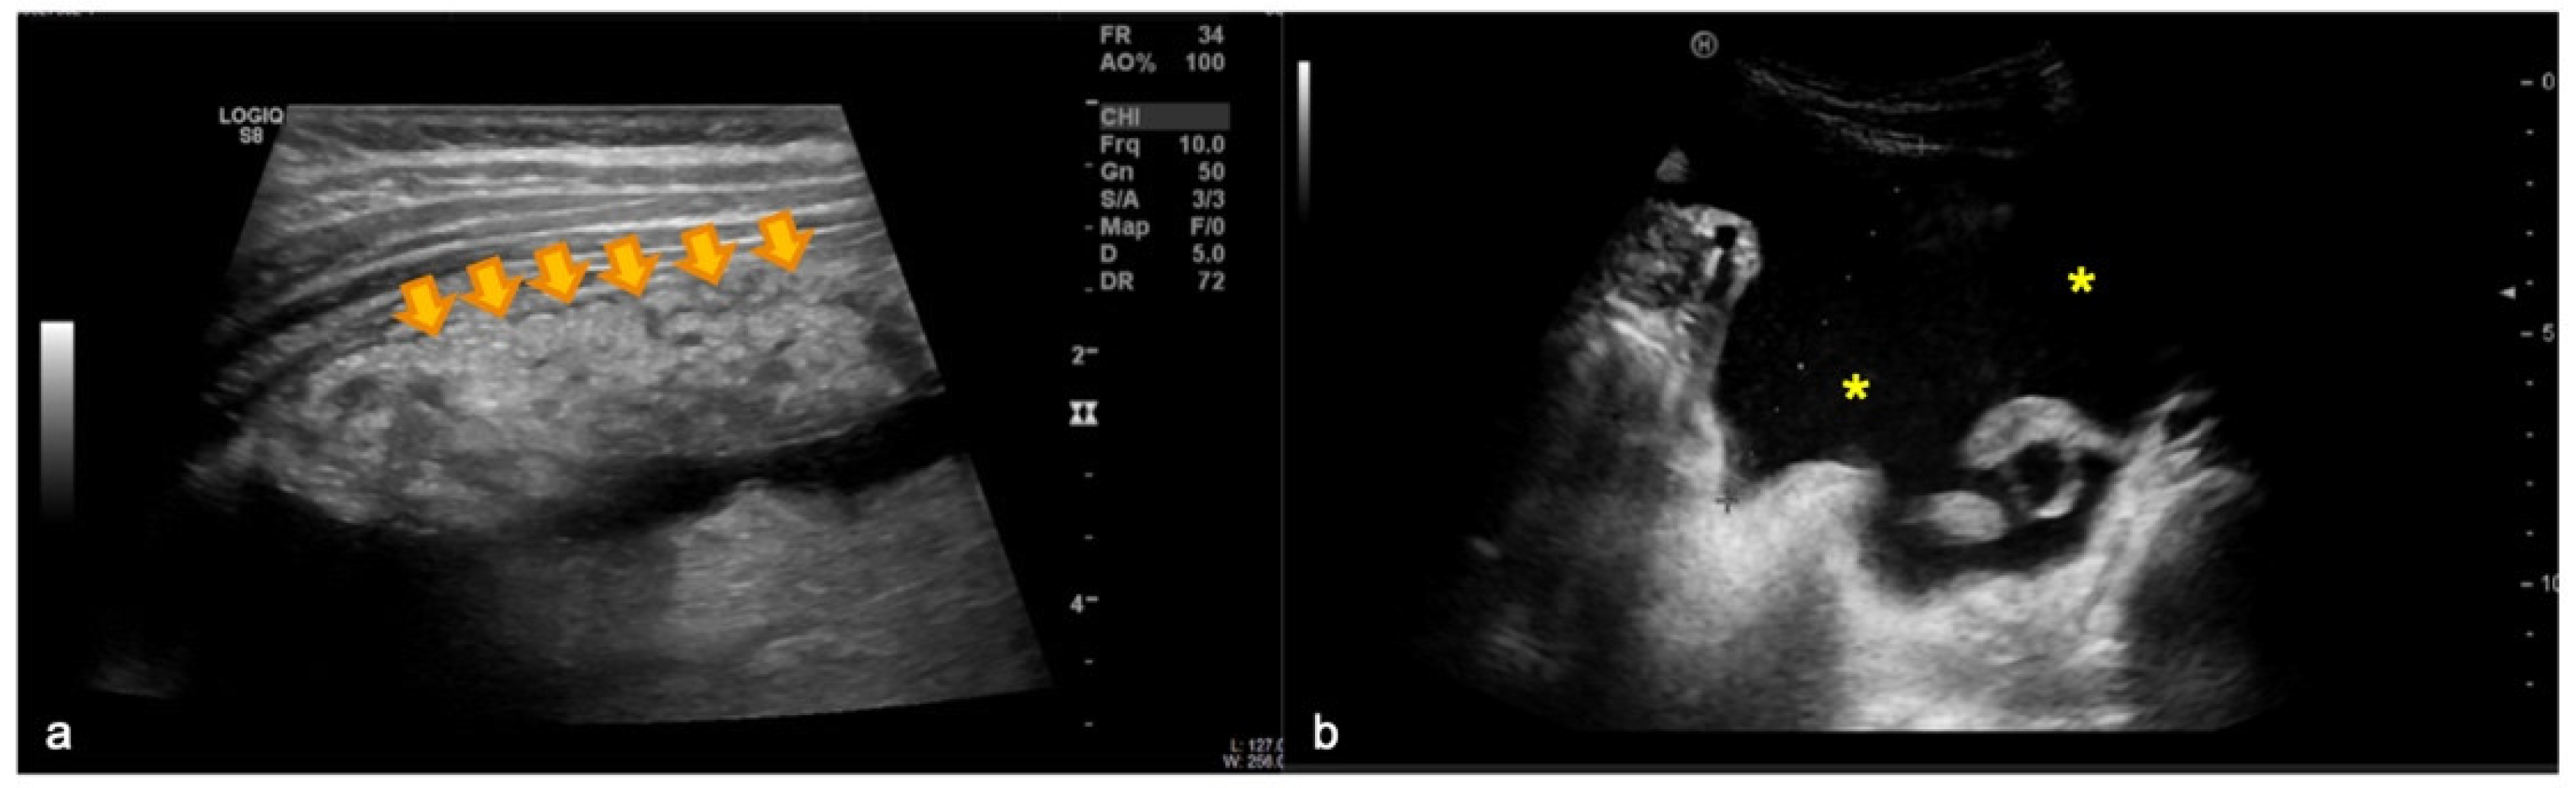

The ultrasound of the right upper quadrant of the abdomen shows

The ultrasound of the right upper quadrant of the abdomen shows What Does Yellow And Orange Mean On An Ultrasound When yellow does appear, it is. Furthermore, the appearance of yellow on an ultrasound raises questions about its. Parents often obsess over what their abbreviations mean and if they are some sort of foreshadowing to who their baby will become. It can also suggest the presence of. Orange is possible when using power doppler ultrasound machines. Yellow or orange color. What Does Yellow And Orange Mean On An Ultrasound.